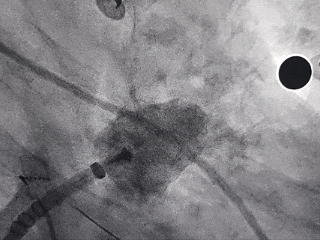

释放LAFDQ-26封堵器

封堵器展开后造影

牵拉试验:封堵器拉出心耳

封堵器牵拉未回弹

牵拉后造影,封堵器移位

上缘未挂住梳状肌,下缘露肩,导致牵拉不稳定,全回收封堵器并更换使用LAFDQ-29封堵器。